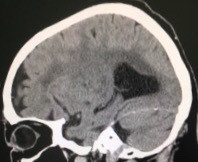

2018/06/05 急に歩けなくなったアルツハイマー症例

改訂長谷川式 11/30 遅延再生 0/6 頭部MRI(受診時)前頭葉と両側海馬の萎縮 錐体外路兆候及び行動異常 認めず。今年、3月初めに転倒。頭部CT上、血腫認めず。4月中旬、代診だったが、トイレに歩いて行けている、夜間に家の中を歩き回って困る等、歩行障害はなかった。5月中旬、「歩けなくなった」と受診。見当はついているので、脳外科を紹介。その返事に同封されていた写真が上のもの。無事にオペも終わり、元気であると、わざわざ、御家族が御礼の挨拶に来院され、近況を聞くことができた。でも、両側に血腫があるとは思っていませんでした。

80歳代 女性。昨年末から診療開始。改訂長谷川式 11/30 遅延再生 0/6 頭部MRI(受診時)前頭葉と両側海馬の萎縮 錐体外路兆候及び行動異常 認めず。今年、3月初めに転倒。頭部CT上、血腫認めず。4月中旬、代診だったが、トイレに歩いて行けている、夜間に家の中を歩き回って困る等、歩行障害はなかった。5月中旬、「歩けなくなった」と受診。見当はついているので、脳外科を紹介。その返事に同封されていた写真が上のもの。無事にオペも終わり、元気であると、わざわざ、御家族が御礼の挨拶に来院され、近況を聞くことができた。でも、両側に血腫があるとは思っていませんでした。